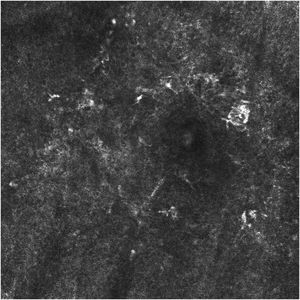

Clinical and dermoscopic images of the lesions were obtained using an iPhone 10 coupled to Dermlite®; and RCM images were obtained with the aid of Vivascope 1500®, before, during, and 60 days after the end of the therapy. Cross-sectional 5 × 5 mm images of the stratum corneum, stratum granulosum, stratum spinosum, and superficial dermis were analyzed by two dermatologists with experience in performing this technique. Additionally, the RCM will be repeated every three months in the first year of follow-up for early diagnosis of possible recurrence.

Dermatological examination showed irregular brownish lesions in photo exposed areas with intense sun damage, and dermoscopy showed an atypical pseudo network (Fig. 1). RCM showed the presence of atypical pagetoid cells in the epidermis and atypical perifollicular dendritic cells, with a loss of the epidermal structure (Fig. 2).

Of the six selected patients, five completed 12 weeks of treatment with IQ 5%, and one patient was lost to follow-up at eight weeks of treatment. After 60 days of the end of treatment with IQ 5%, four patients underwent RCM, and one patient is scheduled to undergo post-treatment RCM. At the post-treatment dermatological examination, evidence of clinical and dermoscopic healing of the lesions was observed (Fig. 3), whereas RCM examination showed the absence of pagetoid and/or atypical cells in the epidermis, absence of perifollicular dendritic cells and a preserved epidermis (Fig. 4).

One of the patients, before participating in the study, had undergone three sessions of cryotherapy for the treatment of LM on the scalp, with clinical and dermoscopic resolution of the lesion. Four months after the last cryotherapy session, there was a recurrence of the lesion, diagnosed through RCM, with the appearance of atypical perifollicular dendritic cells in clinically and dermoscopically healed areas. The patient was then submitted to treatment with Imiquimod for 12 weeks, and the post-treatment RCM was performed, showing resolution of the condition.